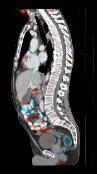

It is prudent to ask whether moving from double precision to single precision on the GPU introduces differences due to rounding. In fact, we observed that this can have an effect (Figure 1). However, it typically only occurs when there are no clear correspondences, such as in regions of the colon with different content, or when the examination table is visible in one of the two scans. In these areas, there is no strong objective function gradient in either direction during optimization, so that numerical differences have a larger impact. However, we argue that if such areas were to be registered accurately, a more elaborate model that accounts for the possible removal of structures would have to be employed in any case.